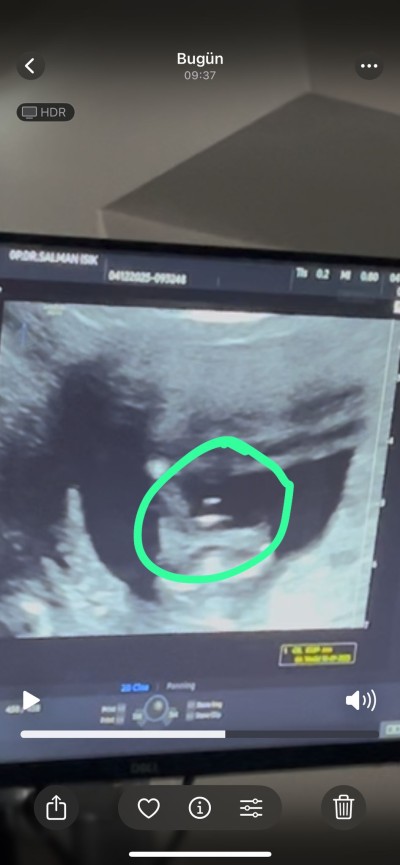

Cinsiyeti hala öğrenemedim kızlar bu 14 haftalıktı bugün 17 oldu devlete gittim o da çok hareketli suan net göremıyorum dedi ben video çekmiştim o görsek de çıkıntı var ama pipi mi başka bişey mi anlamadım

Canım o işretlediğin yer  bacak arasımu arasıysa eğer pipi görünüyor özeller söylüyor aslında cinsiyeti ben 12 de gittiğimde benimkininde bacak arası böyleydi doktorum erkek dedi

Yarın kesin öğrenicem canım ama tahminim yüzde yüz erkek diyor çünkü ultrosonda aynı senin ki gibi belliydi  pipi görünüyordu